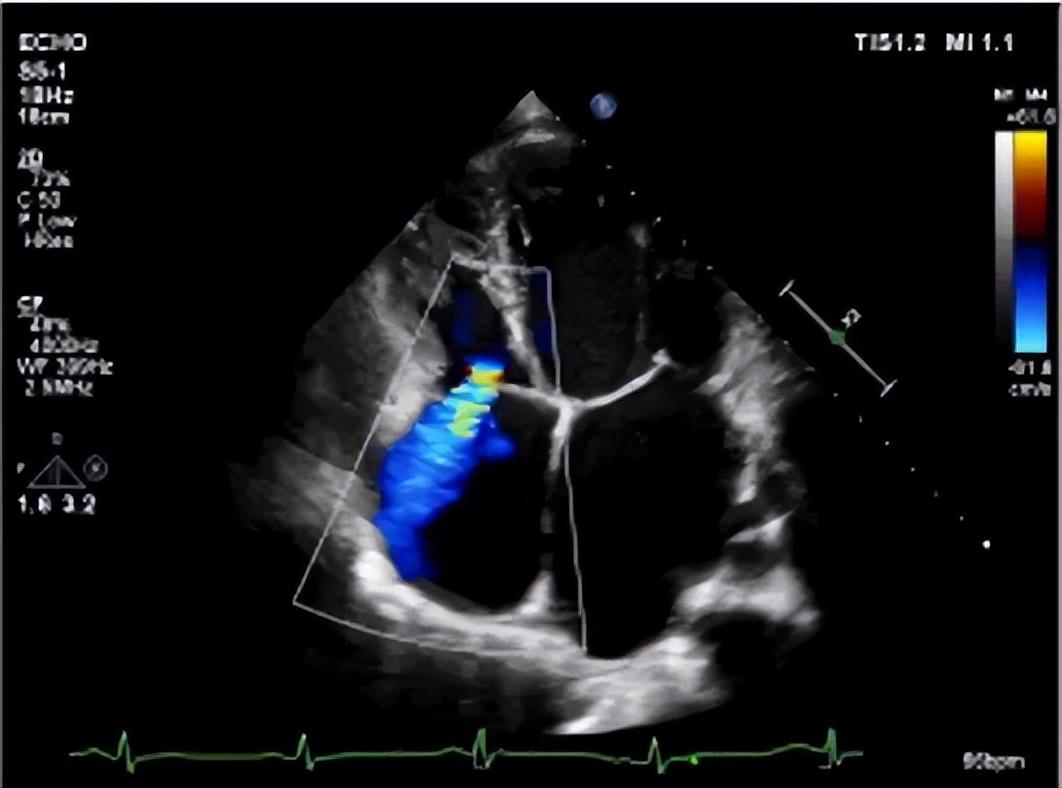

△ 心脏超声显示:全心扩大,左、右室壁运动普遍减弱,二尖瓣重度反流,三尖瓣中度反流

“心衰让他无法平躺,只能坐着睡,右心衰加重,导致胃肠道淤血严重,基本吃不下饭。”

——阜外医院深圳医院

心内科副主任医师 朱佩